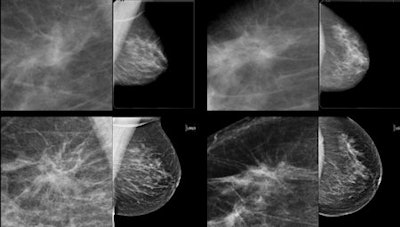

Architectural distortion that was not recalled during screening, but detected on CAD. Top row: Exams that were not recalled during screening: Bottom row: Exams where lesion was detected in a later screening round.